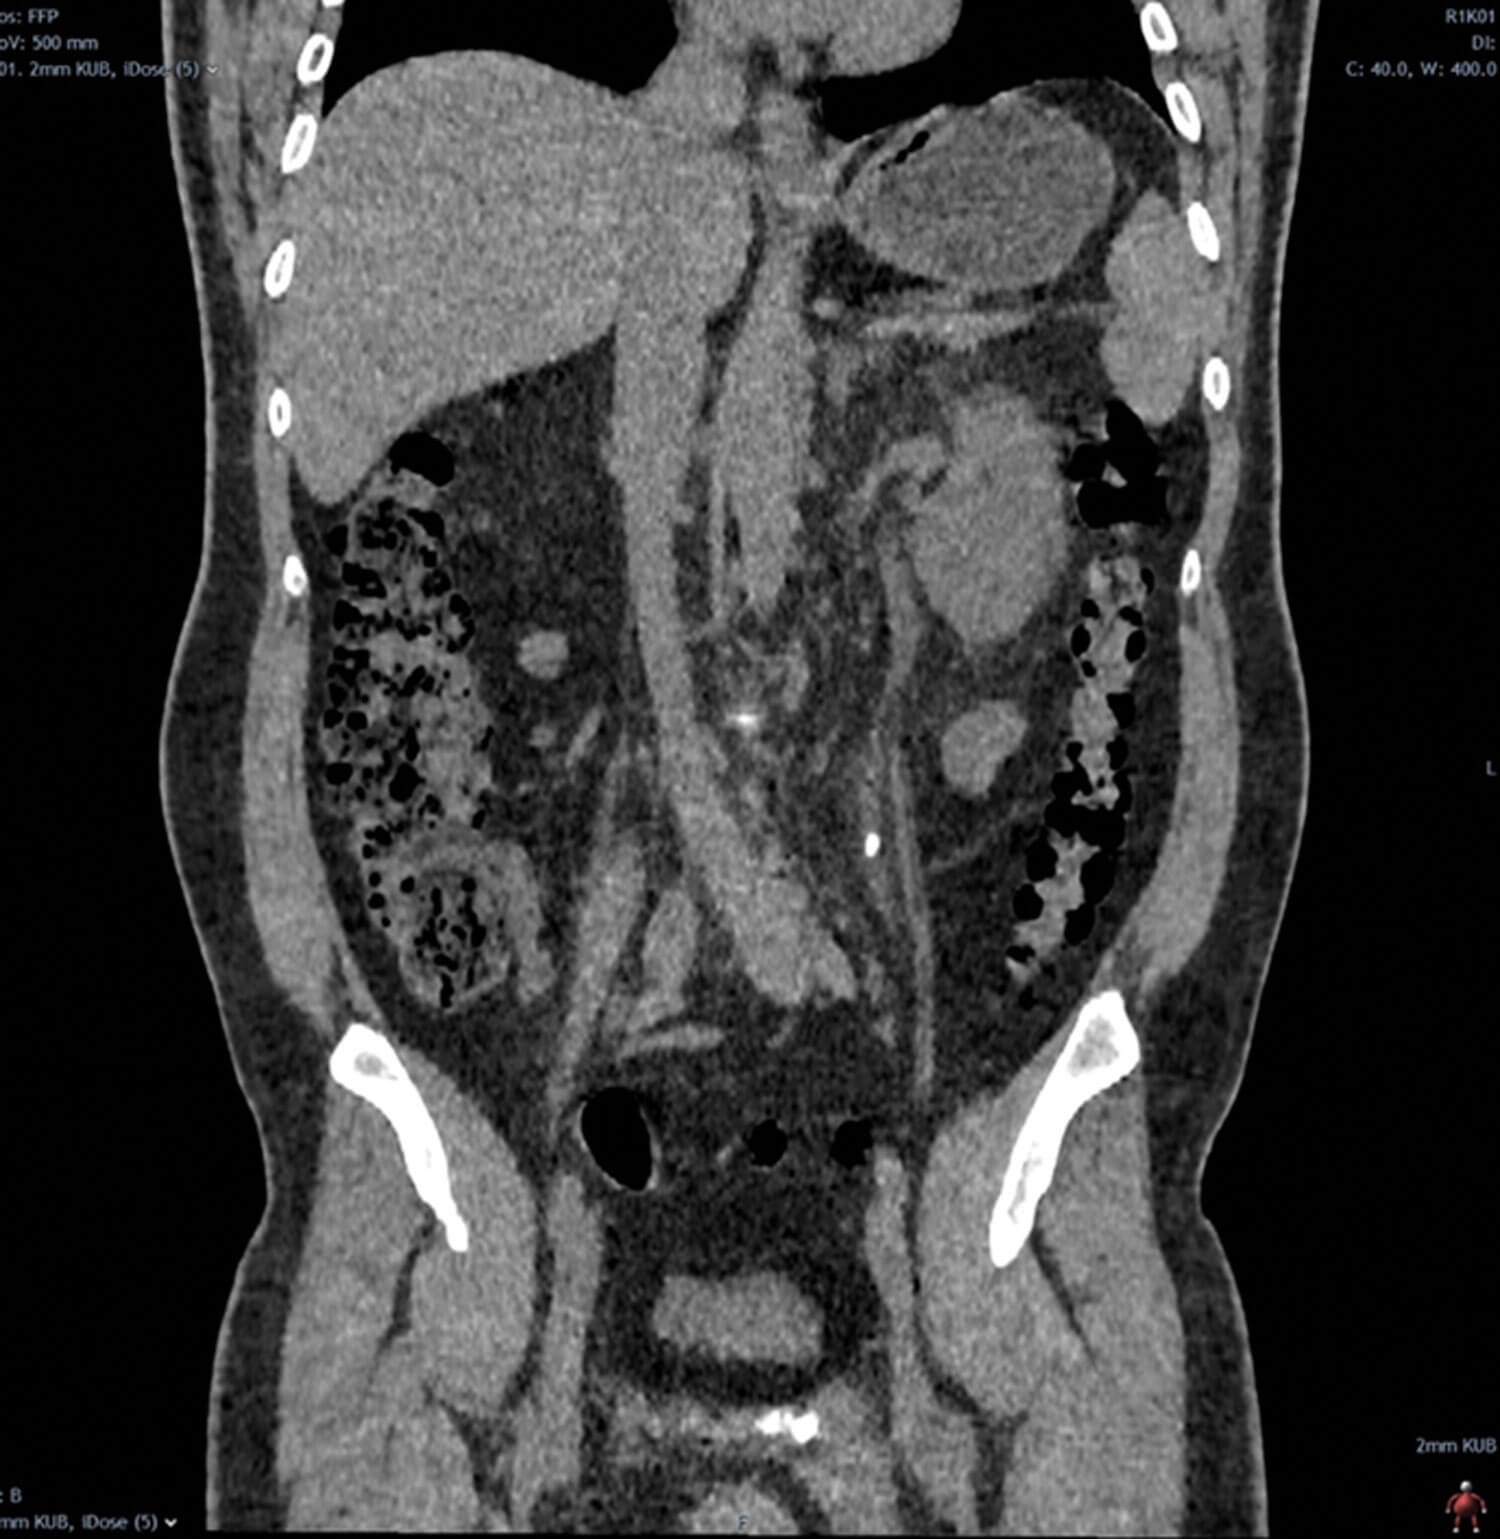

Figure 1.

- Describe Figure 1 and the acute urological diagnosis.

1. This is a coronal reconstruction of an unenhanced low dose CT of kidney, ureter, bladder (KUB) in the soft tissue window which demonstrates a 7mm (craniocaudal length) left upper ureteric calculus with mild upstream hydroureteronephrosis and associated periureteric fat stranding.